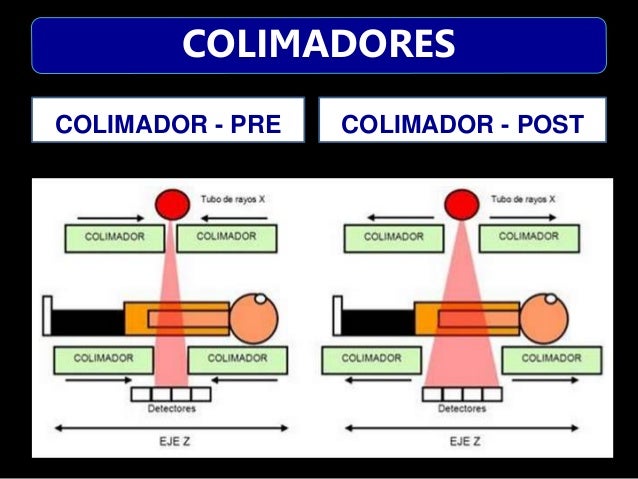

TUBO DE RX

DETECTORES

GANTRY